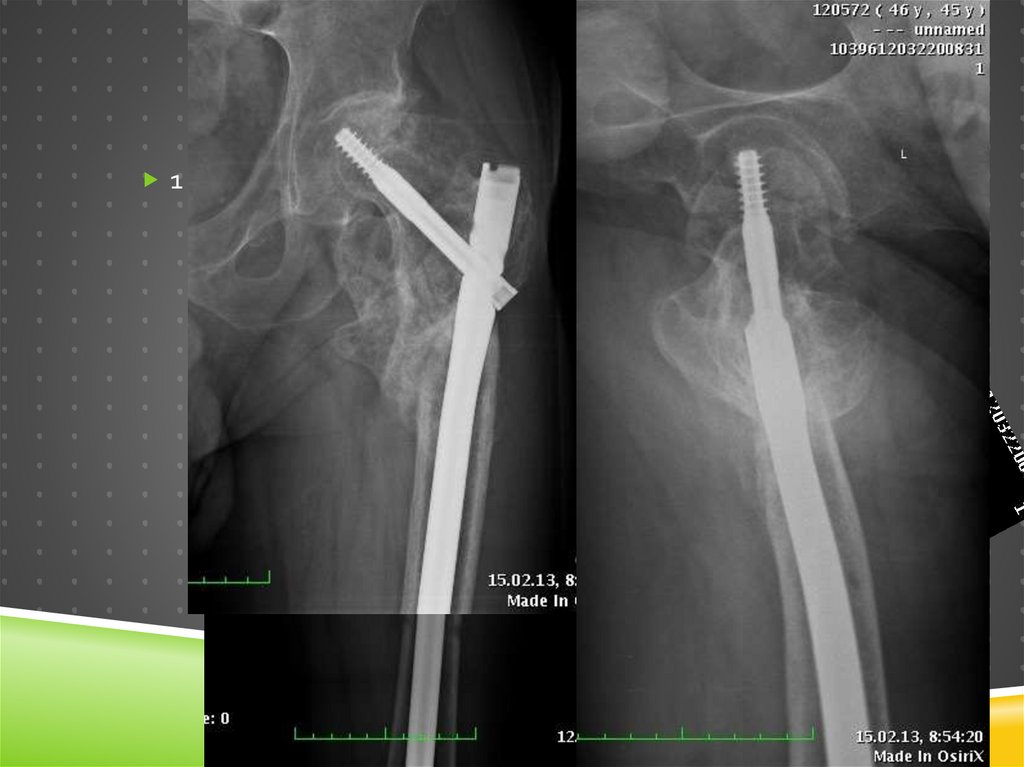

Ревизионный остеосинтез